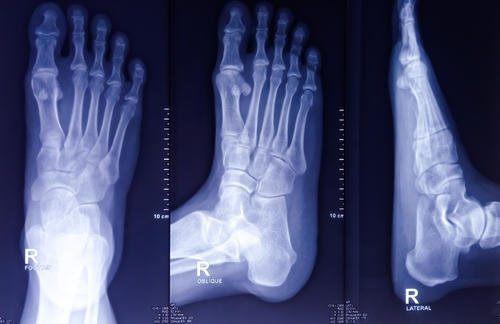

Рентген стопы – это современный и доступный метод обследования свода стоп, позволяющий определить наличие патологических изменений. Обследование основывается на проникновении рентгеновских лучей через структурные слои тканей. Процедура абсолютно безболезненна и не приносит дискомфорта. По итогу, Вы получаете снимок зоны исследования, который выдается вместе с описанием, результаты которого необходимо отдать специалисту для назначения дальнейшего лечения.

Как проходит рентген стопы

Для проведения рентгена стопы в нашем многопрофильном медицинском центре оборудован комфортный диагностический кабинет с современным рентгеновским аппаратом. В первую очередь рентгенолог поможет занять правильное положение, а также наденет на пациента средства защиты органов, не участвующих в исследовании.

В зависимости от анамнеза в направлении специалист самостоятельно выбирает проекции для сканирования:

• В прямом виде – наиболее распространена для диагностики большинства патологических состояний. Стопа устанавливается прямо на рабочий стол, что позволяет четко визуализировать голень, пятку и предплюсны;

• Боковом – используется для диагностики травматических повреждений, а также плоскостопия. Сканер устанавливается в боковой части ноги;

• Косом – в данном случае нога стоит прямо, но перемещается сам источник излучения. Данный вариант может понадобиться для более детального снимка передней части стопы.

Расшифровка результатов

Как только получен качественный снимок, врач-рентгенолог обязательно выполняет описание анатомических особенностей свода стопы в разных проекциях. Главное, что должно быть зафиксировано в заключении – это наличие переломов, новообразований, очагов воспалительного процесса и иных отклонений от нормального развития костей и тканей.

Основное, что поддается описанию на рентгене стопы, это:

• Плоскостопие. Это заключение возможно получить при выполнении обследования стопы с нагрузкой. Для этого, нога устанавливается на специальную подставку внутренней стороной по отношению к кассете рентгеновского аппарата. Результаты определяются по расчетам высоты линий от пальцев стопы до пяточной кости и градуса расположения. В норме эти значения для взрослого человека должны быть равны 35 мм и 125-130°.

• Травмы и переломы. На рентгенографическом снимке, подобные отклонения визуализируются как затемнения с неровными, нечеткими контурами. Для более детального заключения в отношении локализации, необходимо дополнительно выполнить пальцевое обследование проблемной зоны.